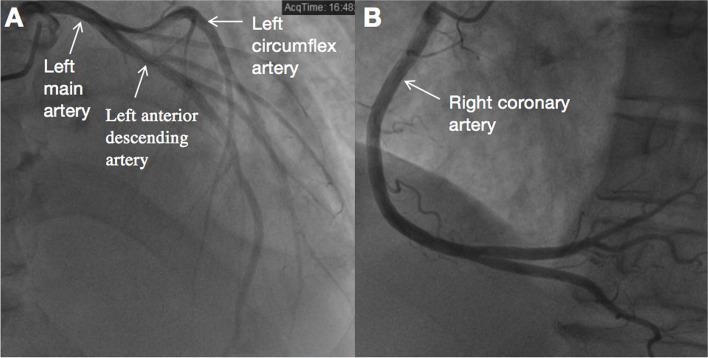

A 64-year-old male presented with chest discomfort and dyspnea on exertion lasting the past six months. Physical examination revealed a grade 4/6 continuous biphasic murmur along the left sternal edge and a grade 3/6 systolic murmur at the apex. Transthoracic echocardiography (TTE) demonstrated: (1) an AVT with three orifices, i.e., one aortic opening, one LV opening, and one RV opening. The LV and RV openings were located in the left and right ventricular outflow tracts, respectively. (2) The aortic valve (AV) was calcified with a small aneurysm at the non-coronary cusp. (3)The mitral valve (MV) chordal rupture of the P2 and P3 segments was observed in the posterior leaflet with severe eccentric regurgitation. Subsequent coronary computed tomography angiography (CTA) further confirmed the diagnosis of AVT with three openings, and clarified the coronary arteries normally arose from the aortic sinuses. The patient was then referred for surgical treatment, consisting of closure of three AVT orifices, AV replacement, and MV replacement. Six months following surgery, the patient was asymptomatic. TTE demonstrated normal mechanic AV and MV function, and there was no residual shunt among the ascending aorta, LV and RV.

一名 64 岁男性因过去六个月持续出现胸痛和劳力性呼吸困难而就诊。体格检查发现胸骨左侧缘有 4/6 级连续双期杂音和心尖处 3/6 级收缩期杂音。经胸超声心动图(TTE)显示:(1)具有三个口的 AVT,即一个主动脉口、一个 LV 口和一个 RV 口。LV 和 RV 口分别位于左、右心室流出道。(2)主动脉瓣(AV)钙化,无冠状动脉瓣有小动脉瘤。(3)二尖瓣(MV)后叶 P2 和 P3 节段腱索断裂,伴有严重偏心反流。随后的冠状动脉计算机断层血管造影(CTA)进一步证实了具有三个口的 AVT 的诊断,并明确了冠状动脉正常起源于主动脉窦。随后患者被转诊接受手术治疗,包括关闭三个 AVT 口、AV 置换和 MV 置换。手术后 6 个月,患者无症状。TTE 显示机械性 AV 和 MV 功能正常,升主动脉、LV 和 RV 之间无残余分流。